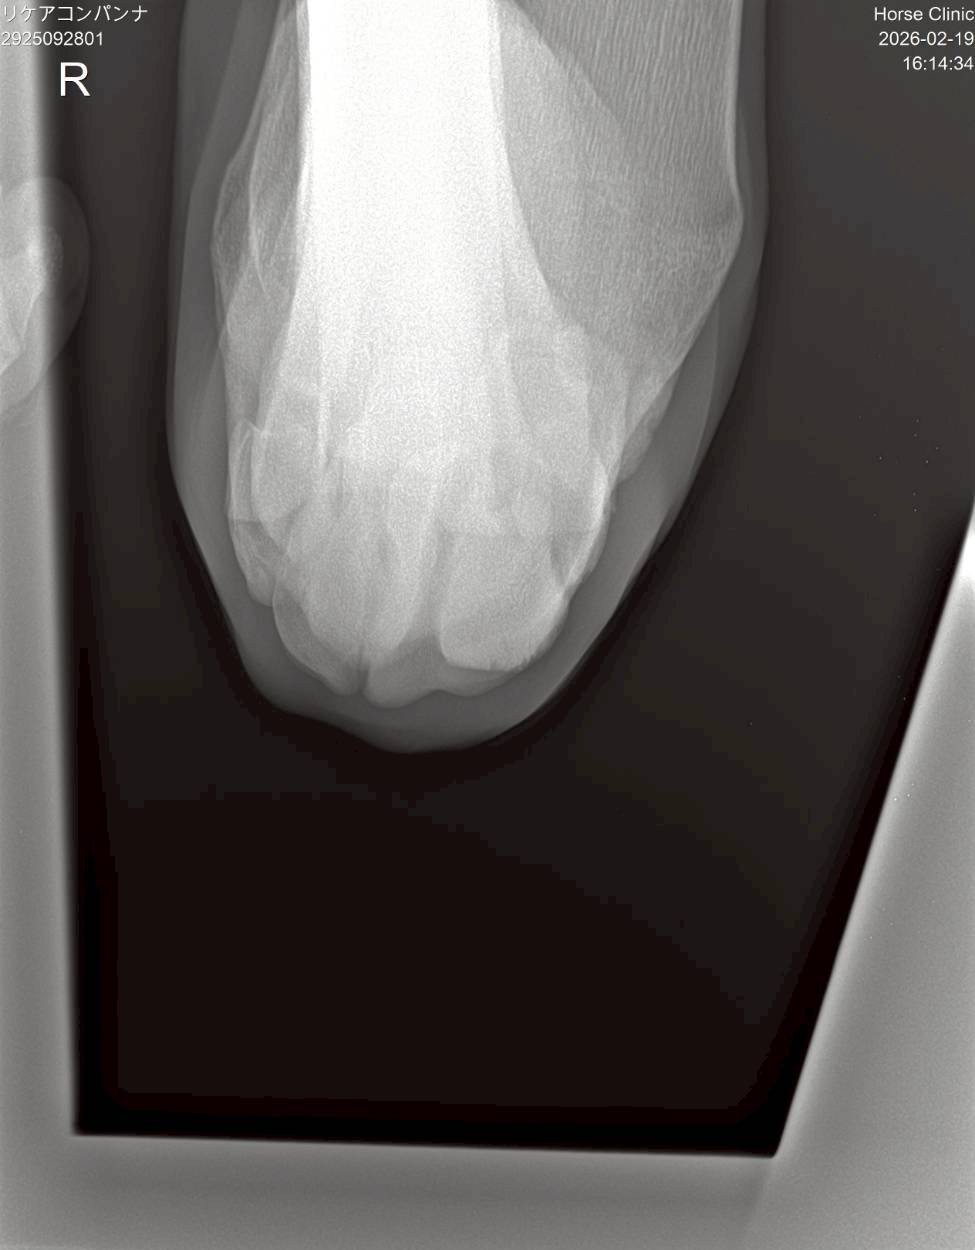

昨年8月の前走で右前肢の橈骨遠位端骨折を発症してしまいました。見舞金9号(競走中6カ月)を受給したうえ、手術は受けていません。休養を取って立ち上げ、現在は周回コースでキャンター2500mを18―18で、週1回は坂路で1本15―15を消化中。馬体重は2月16日の測定で500㎏です。

※2025年8月19日の競走で右前肢橈骨遠位端骨折を発症。事故見舞金9号(競走中の事故により事故発生の日から6ヵ月以上中央競馬の競走に出走できなくなった場合)を受給しています。